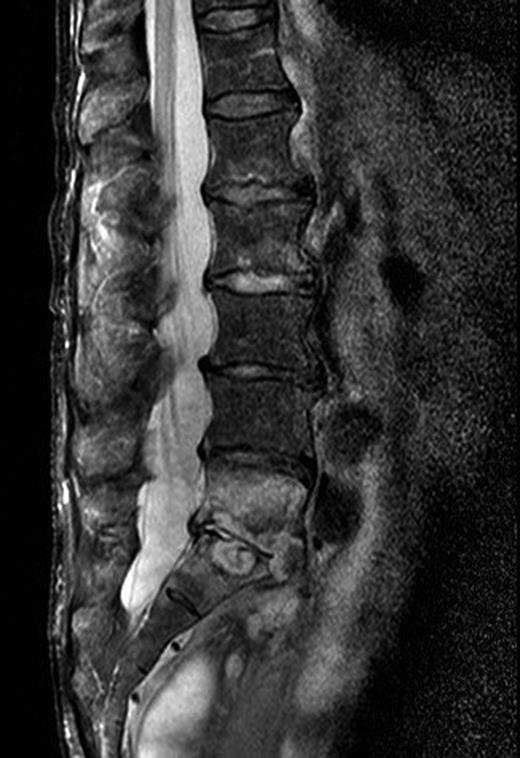

Three months after the initial operation, the patient presented with severe back pain radiating to both legs. The lower lumbar spine was highly tender on percussion, but the neurologic examination revealed only a slight loss of muscle strength in the big right toe. Vascular diseases of the lower extremities were excluded. The patient did not have fever at any time. Leucocytes were normal and CRP was moderately elevated to 42 mg/l. The MRI of the spine now revealed vertebral discitis without epidural abscess formation (Fig. 1). A barium enema excluded fistulas to the rectum (Fig. 2). Culture of CT-guided needle biopsy was positive with P. aeruginosa and antibiotic therapy with 6× 1 g Ceftazidime i.v. per day was started. The pain slowly improved and CRP values declined. After 20 days, the patient developed β-lactam-associated neutropenia. Therefore, treatment was changed to oral ciprofloxacin and continued for another 9 weeks. Pain was managed with fentanyl skin patch, paracetamol, metamizol and pregabalin. The patient fully recovered from the lower back pain. The loss of muscle strength in the big right toe persisted and was interpreted as stenosis of right S5 foramina due to infective destruction which did not require neurosurgical decompression.

If a vertebral discitis is suspected, an MRI of the affected area should be performed. This is the gold standard with sensitivity, specificity and accuracy of 96, 92 and 94%, respectively. Typically, MRI shows decreased signal intensity of vertebral bodies in T1-weighted images and increased disc signal intensity in T2-weighted images. However, MRI may be negative early in the disease course and should be repeated after 7–14 days if the diagnosis is still likely. In the absence of positive blood cultures with a typical microorganism CT-guided biopsy for microbiology and histology should be performed before initiation of empiric antimicrobial therapy. The sensitivity of cultures from biopsy is described from 36% up to 100%. Blood cultures alone are positive in 72% [4]. If microbiological culture of a representative biopsy remains negative for >5 days, broad spectrum bacterial DNA amplification may help to identify a causative microorganism, particularly if antibiotics had been administered before biopsy [6].